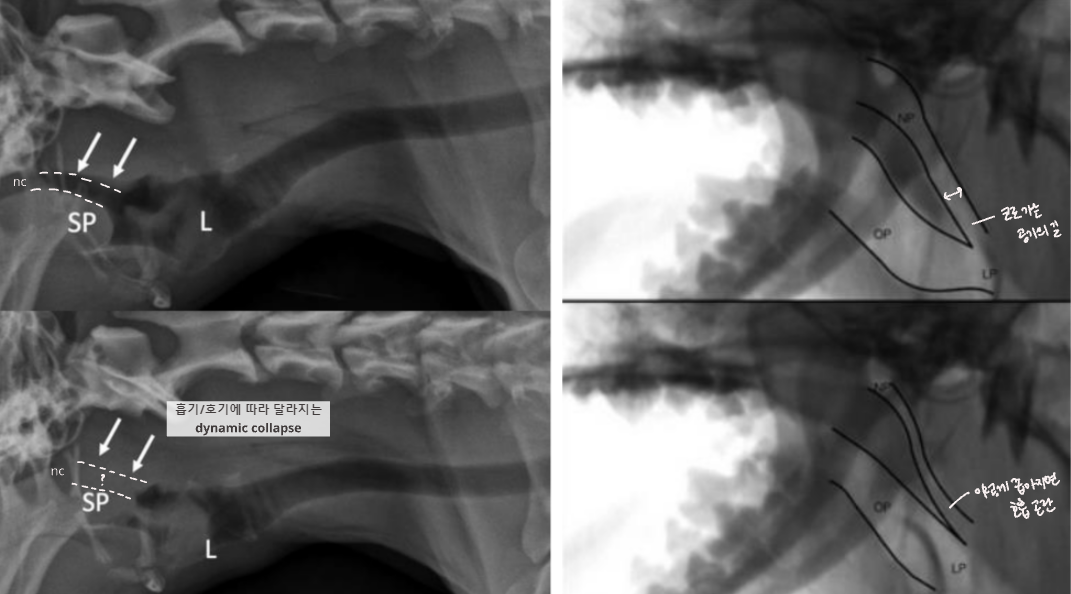

Tracheal Collapse (TC, 기관 허탈)

Tracheal collapse

원인 : 주로 연골연화증(chondromalacia)

증상 : Goose-honking sound (grade 3 이상에서)

치료 : 1) 체중 감량 - 2) 약물 - 3) stent 장착

Static : 주기 상관없이 계속 무너져 있음

Dynamic : 호기/흡기에 따라 달라짐

많이 무너지는 위치

Cervical : 흡기에는 경추 쪽이 많이 무너짐 (thoracic inlet)

Intrathoracic : 호기에는 흉강 압력이 증가하여 흉강 쪽이 무너짐

TC - pitfalls (오진 유의)